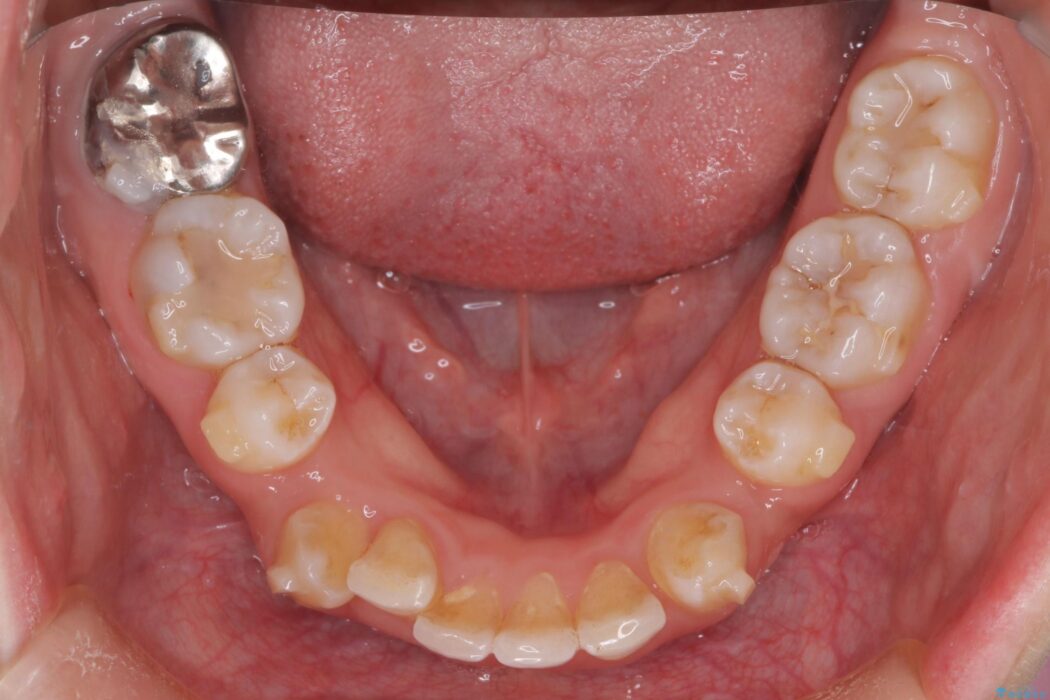

治療後について

長年の悩みだった重度の乱れが解消され、口元の突出感もすっきり改善。見た目も機能も安定した、理想的な歯並びを獲得していただけました。